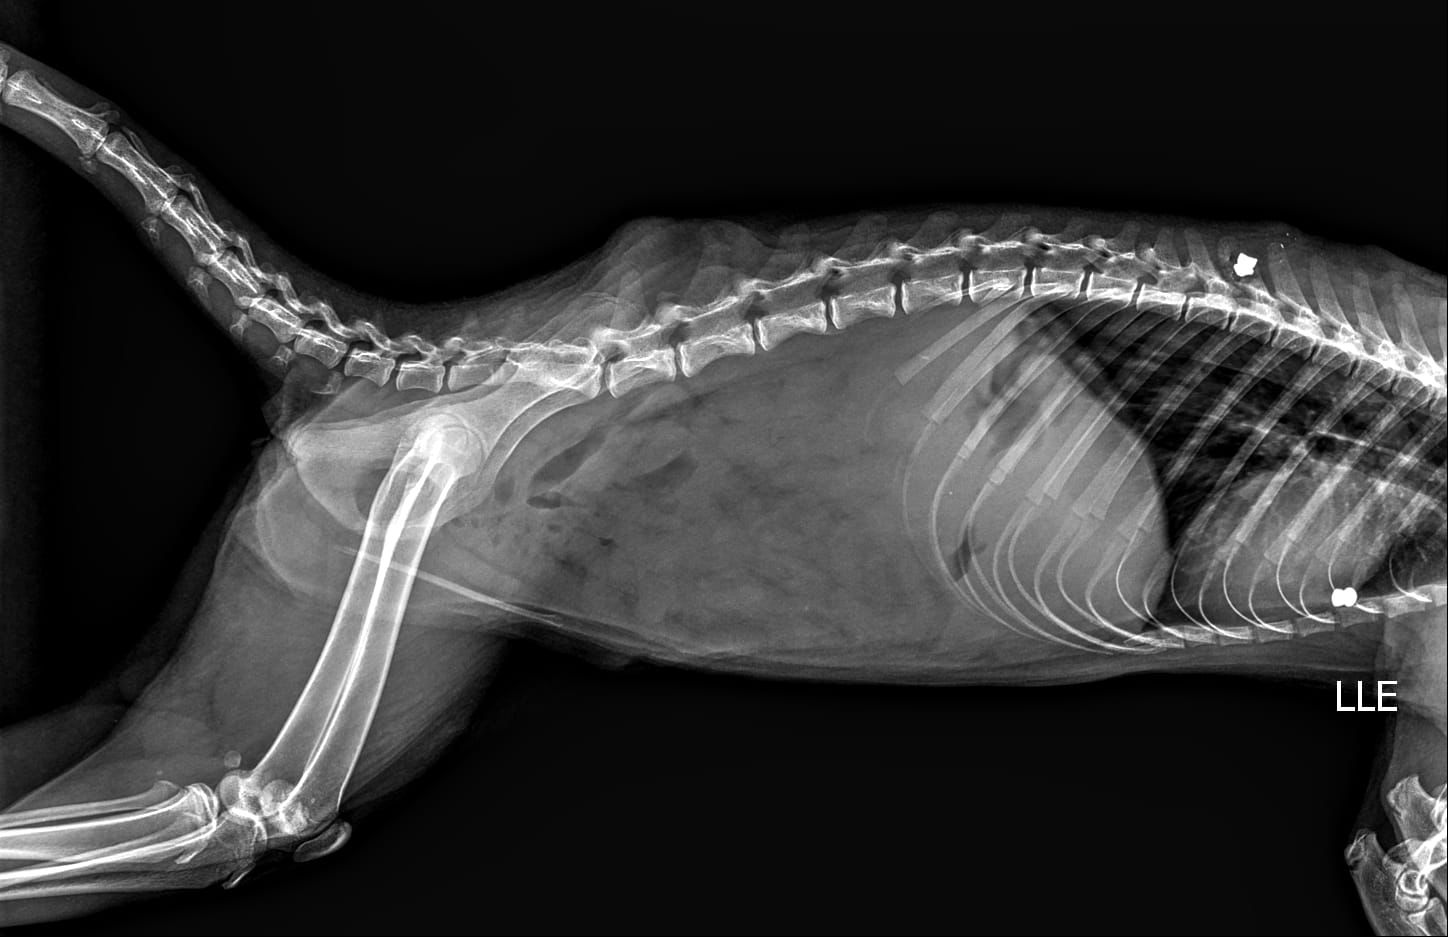

Além da preocupação ambiental, a Secretaria alerta para casos de maus-tratos registrados na região. Há relatos de quatis atingidos por disparos de espingarda de chumbo, incluindo uma fêmea com projéteis alojados no corpo, inclusive na região da coluna vertebral.

Um dos casos está sendo acompanhado pela médica veterinária do Bosque Municipal, Dra. Melissa Campitelli, que, após exame de raio-x, identificou dois chumbinhos alojados no corpo de um dos animais (foto).

A prática configura crime ambiental, e a Prefeitura informou que irá formalizar denúncia junto à Polícia Ambiental.